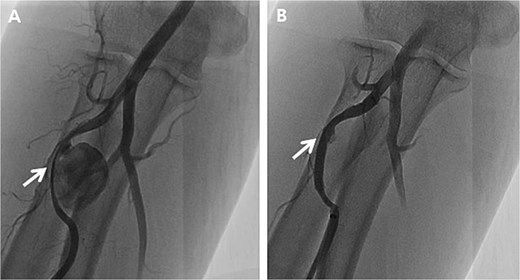

Initially, we conducted percutaneous endovascular exclusion of the proximal RAP using 3.5 × 26 mm Graftmaster covered stent (Abbott Vascular, Santa Clara, CA, USA) and observation of the distal RAP (Fig. 2). Nevertheless, no improvements were observed in the RAPs for 2 weeks after the procedure. A follow-up CT showed the distal migration of the covered stent and increased size of the RAPs. Distal lesion size increased from 0.8 cm to 1.5 cm (Fig. 3A) and the proximal lesion increased from 2.0 cm to 4.0 cm (Fig. 3B). At this point, surgery was considered suitable for the patient to achieve complete recovery.

Peripheral angiography of the right upper extremity. (A) Pseudoaneurysm at the proximal radial artery (arrow); (B) Complete occlusion of pseudoaneurysm after covered stent placement (arrow).